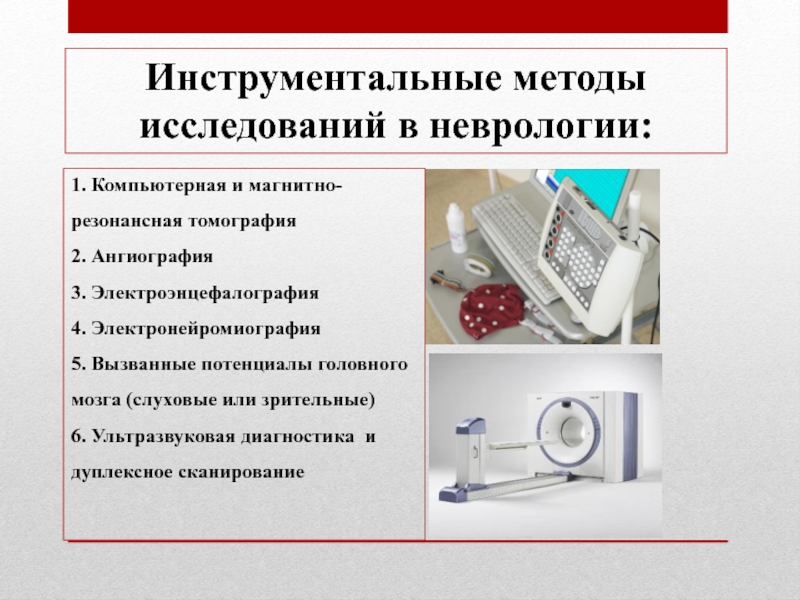

Лучевая диагностика в неврологии презентация - 88 фото